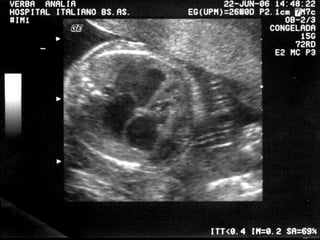

DERRAME PLEURAL

DERRAME PLEURALY O

PERICARDICO.

•UNILATERALES.

• BILATERALES.

•PEQUEÑOS.

•GRANDES.